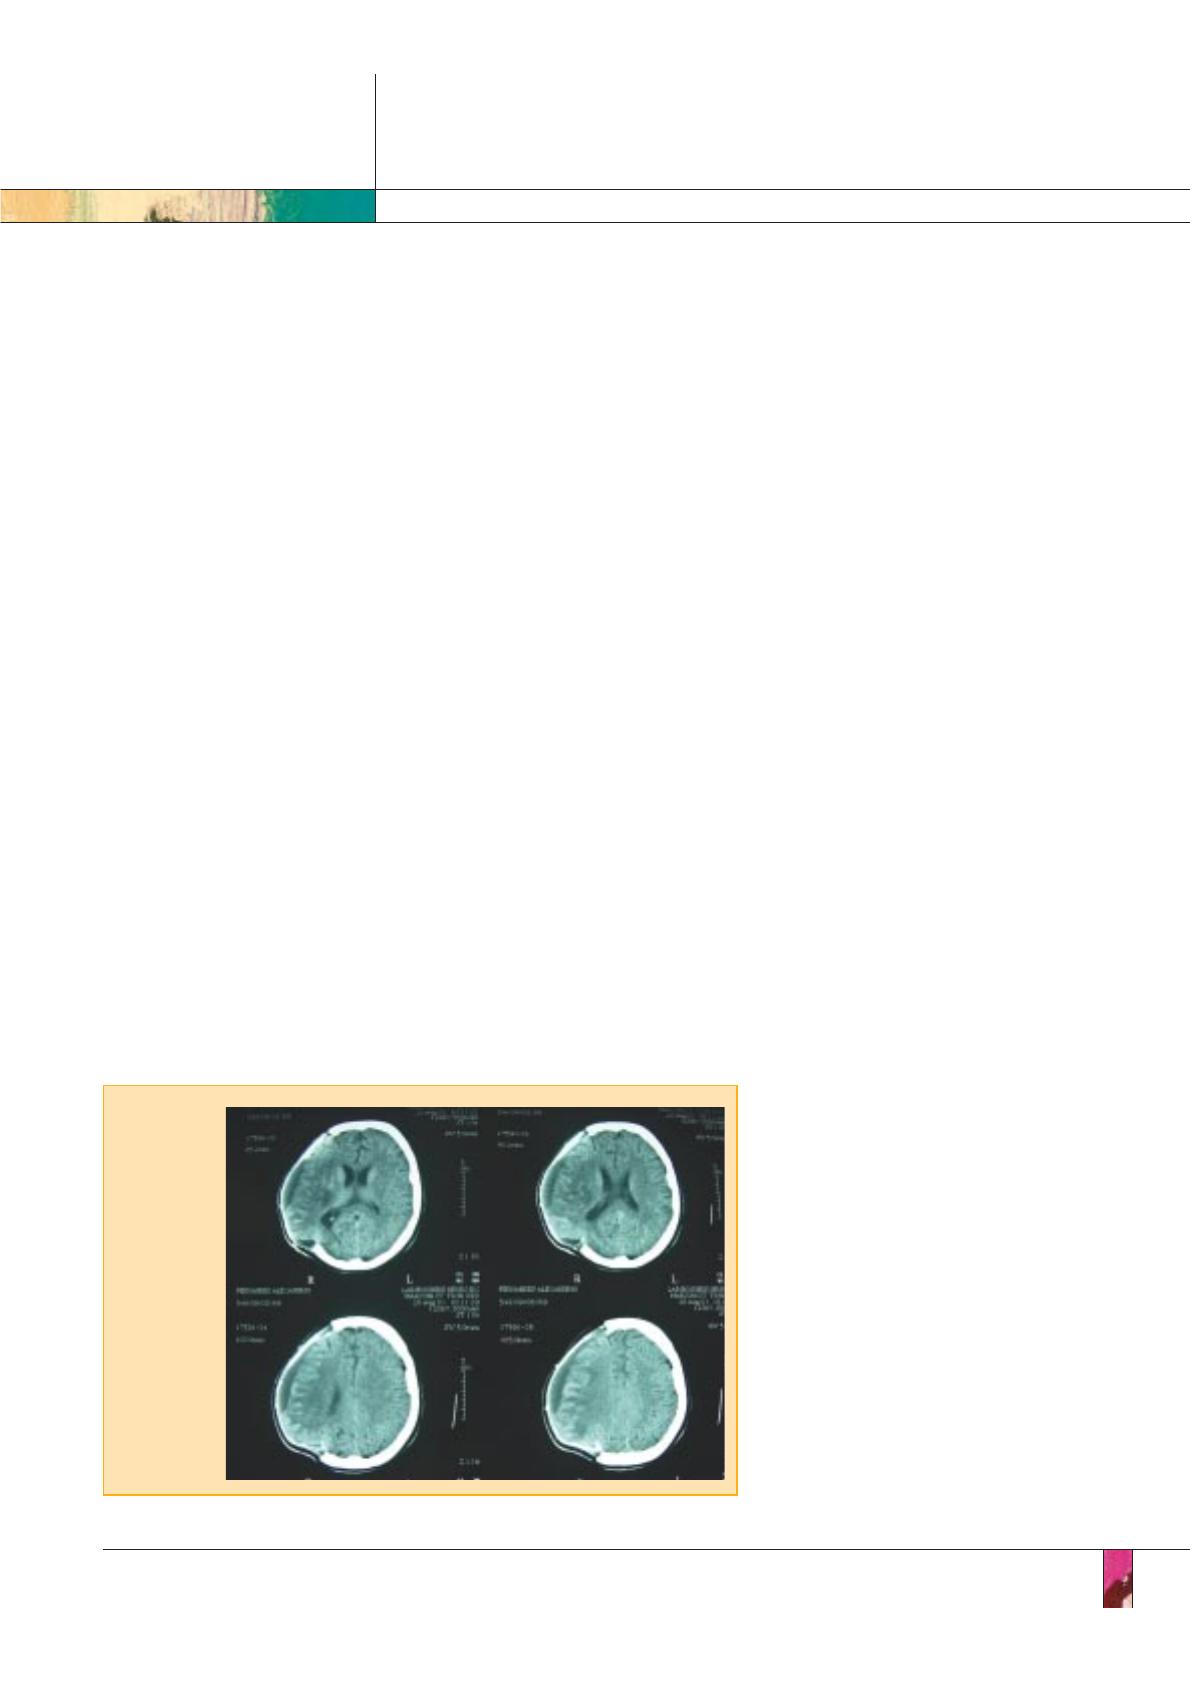

Infarctus sylvien

malin

crâniectomisé

(collection du

Pr P. Amarenco).